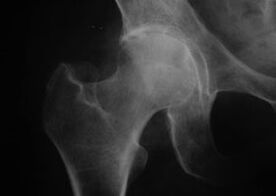

Appearance of joints with arthropathy

hip arthropathy, hip arthrosis

With this disease, typical clinical manifestations of arthropathy can be observed.

The first symptom of hip arthritis is discomfort in the hip joint after physical activity.

With progressive hip arthritis comes increased pain, stiffness, and limited mobility.

Patients with severe hip disease should protect the affected limb, avoid stepping on it, and choose a position that minimizes pain while at rest.